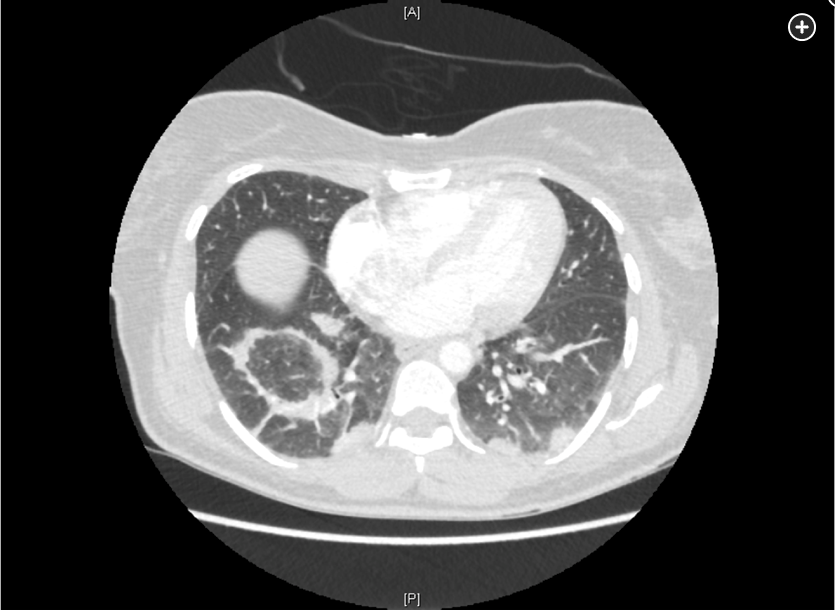

- Early CT of the chest in patients with suspected invasive pulmonary aspergillosis—with typical findings suggestive of septic emboli (nodules, often with a “halo sign”), thromboembolic pulmonary infarction (wedge-shaped peripheral densities), or necrosis with cavitation and a crescent sign—and the serum galactomannan assay can be useful in establishing a presumptive diagnosis of invasive infection, especially in neutropenic patients and hematopoietic stem cell transplant recipients, in whom the assay has a sensitivity of approximately 80%.

Diagnosis of invasive aspergillosis would ideally be based on tissue biopsy showing invasion with organisms showing the typical acutely branching hyphal morphology consistent with Aspergillus species and positive culture (see Figure 4). Biopsy is often not possible in patients who are critically ill, and alternative diagnostic methods may be employed. Testing for fungal antigens such as galactomannan or β-D-glucan can be performed on serum and/or BAL fluid, and a serum polymerase chain reaction test is available from reference laboratories. Serum tests for galactomannan and β-D-glucan were strongly positive in this patient. Radiologic findings can also strongly suggest a diagnosis of invasive fungal disease. Often, there are dense nodular infiltrates (as seen on the CT scan performed on this patient), and there may be halo or reverse halo signs. The halo sign consists of ground glass density surrounding a dense nodule, as shown in Figure 5. It is thought to correlate with areas of hemorrhage surrounding denser areas of active infection, and pathologically invasive aspergillosis is characterized by areas of hemorrhage and infarction. The reverse halo sign, which was present on the CT scan of this patient (see Figure 6, arrow), is described as a rim of high attenuation surrounding an area that likely represents infarction.

Symptoms of IPA are nonspecific and usually mimic bronchopneumonia: fever unresponsive to antibiotics, cough, sputum production, and dyspnea. Patients may also present with pleuritic chest pain (due to vascular invasion leading to thromboses that cause small pulmonary infarcts) and hemoptysis, which is usually mild. IPA is one of the most common causes of hemoptysis in neutropenic patients. Chest x-ray may not detect early-stage disease (ie, small nodules). Chest computed tomography (CT) scan shows single or multiple nodules with or without cavitations and “halo sign” (nodules surrounded by ground-glass infiltrates). Diagnosis is suggested by culture and histology.